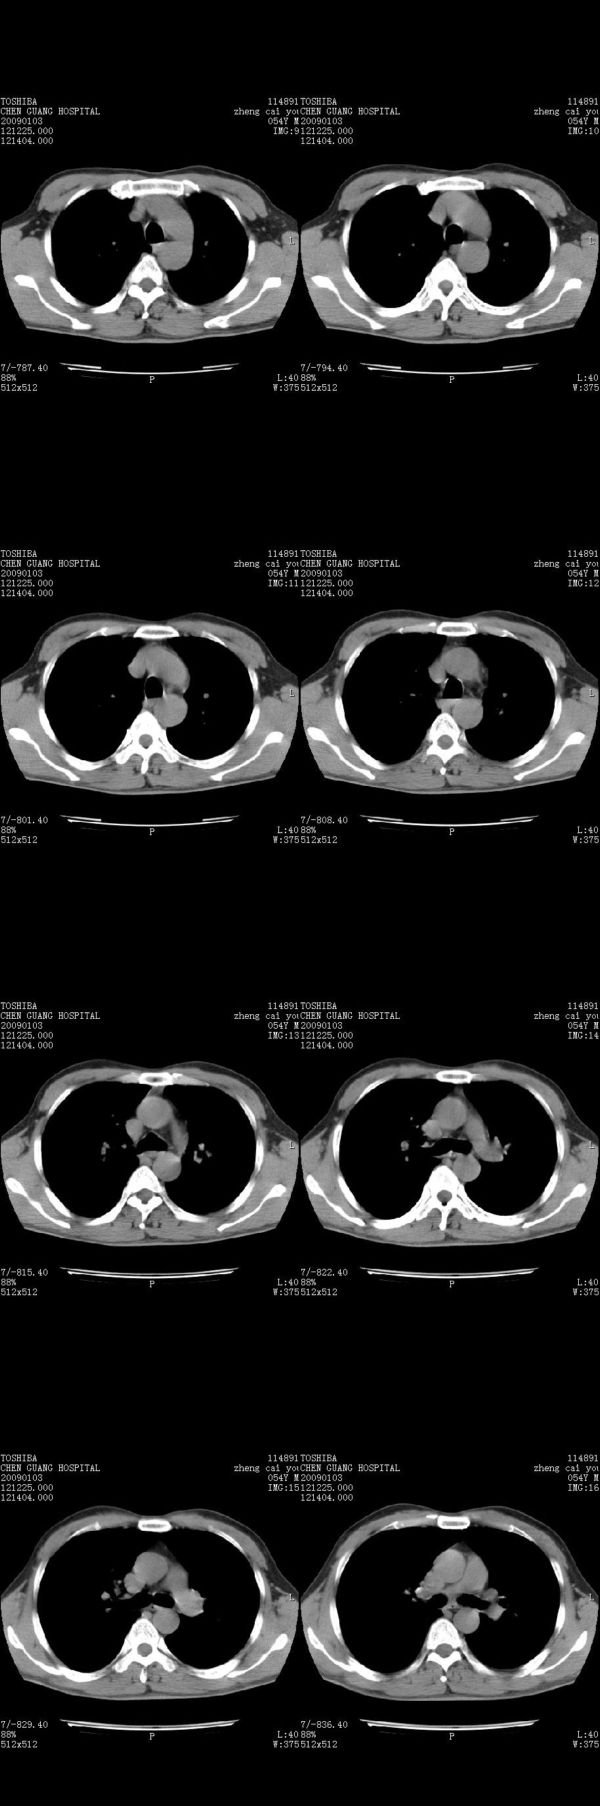

男,54岁,右侧胸部疼痛,平时吸烟,有抽烟后咳嗽咯痰史。昨天没把xiphoid软件吃懂,所以没把纵隔窗图像处理出来!请各位老师帮忙看一下右肺门有没有问题?谢谢!!!!!!!!!!

右肺上叶后段近气管旁仍可见一结节灶,不除外为肿大的淋巴结影。

气管前腔静脉后似见增大淋巴结影,肺门区未见明显肿块影。肺窗示右肺中叶外侧段透亮度增高,可过一段时间再查一下对比一下,毕竟是自己的至亲,又有条件,辐射就顾不得了。

为什么没有肺窗,我觉得右肺上叶前后段支气管间应该加扫薄层,还是小心点吧,其他到没有什么问题

也觉得还好吧,只是右下肺动脉显粗了点,纵膈有钙化淋巴结,再有肺窗就更好了

各位老师:奇静脉增宽,肺上未见明显实变,这还需注意观察些什么?????

右侧肺门影增大,不除外增大淋巴结可能